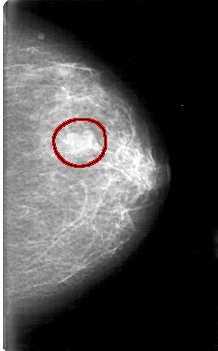

D_4075_1.RIGHT_MLO

FILE: D_4075_1.LEFT_MLO.OVERLAY

TOTAL_ABNORMALITIES 1

ABNORMALITY 1

LESION_TYPE MASS SHAPE LOBULATED MARGINS CIRCUMSCRIBED

ASSESSMENT 0

SUBTLETY 5

PATHOLOGY BENIGN

TOTAL_OUTLINES 1

BOUNDARY